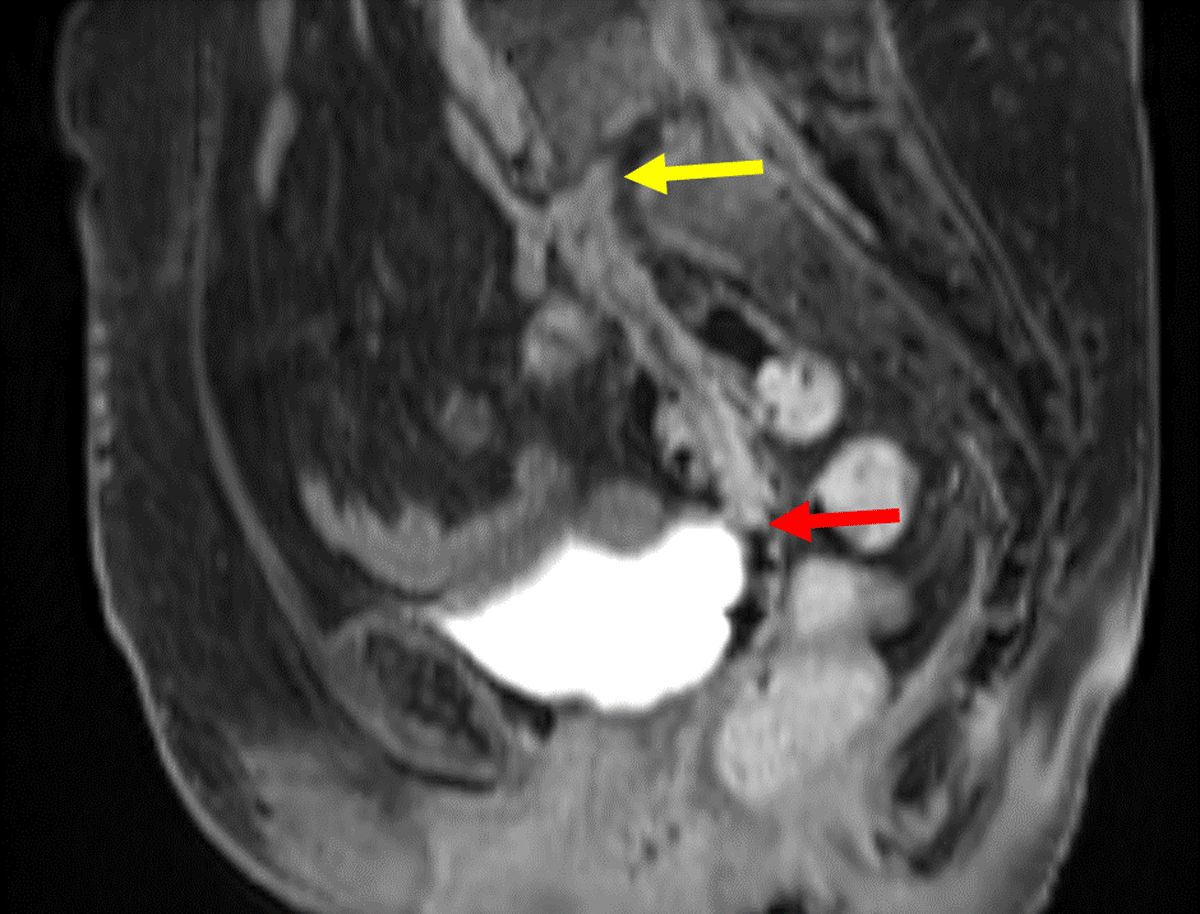

Figure 10

Sagittal contrast MRI in T1 weighting: Pre-operative MRI showing an epidural collection behind the vertebral body of L5 and within the L5-S1 disk (yellow arrow), fistulising into the vagina (red arrow).